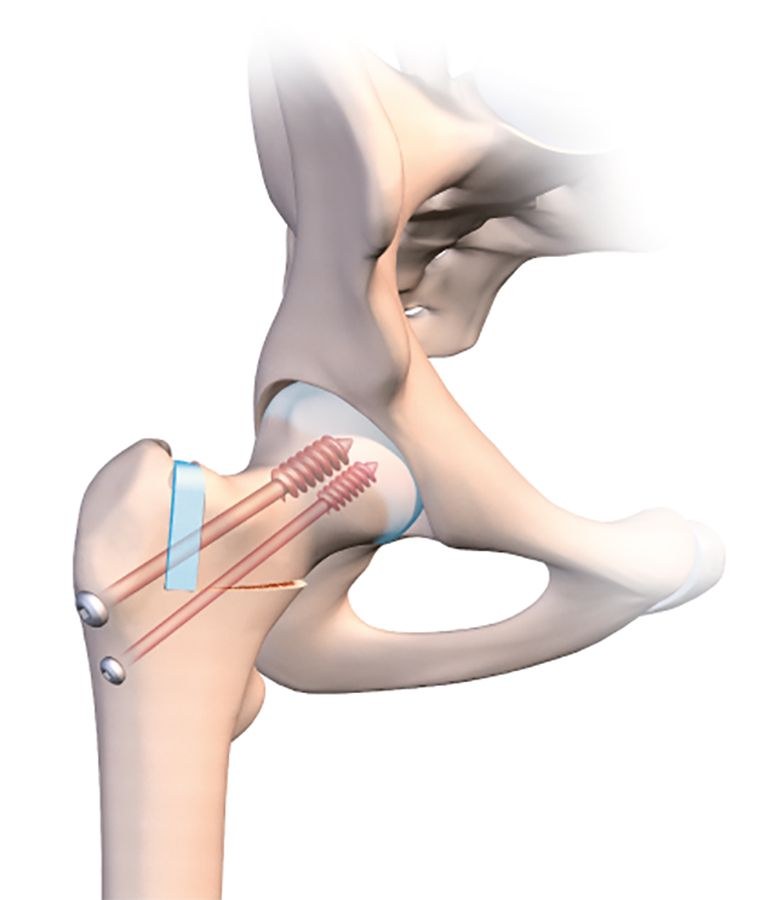

For a valgus-producing osteotomy, the technique is even simpler. One single osteotomy line is required in the medial half of the femur (Fig. 3a).

Simply applying traction along the line of the femur will naturally cause the osteotomy line to open. The line should be incomplete, and the lateral part should again be created as for a guided bone fracture. The medial section of the line is then opened by putting the orthopaedic table in traction.

However, the fixation process is trickier, because the cannulated screw must not create any new compression which would close the line (Figs. 3b, c, d). I recommend using a large diameter fully-threaded cortical screw as close as possible to the medical cortex into the femoral neck where the bone stock quality is highest. A second more lateral screw will maintain a good degree of compression on the lateral part of the line. In addition, here the screw will embed into the cancellous bone of the greater trochanter.

It is quite possible and even desirable to improve the outcome and avoid any loss of correction upon weight-bearing, to insert a hydroxyapatite wedge into the open line (Fig. 3e).

A wedge could be harvested from the iliac crest in order to fill the gap, but this would be insufficient on its own to produce the desired degree of valgus. When the patient tries to bear weight on the region, the line will be unable to close and crush the wedge. The medial-most fully-threaded screw will be more effective if seated in the lateral cortex of the lateral diaphysis and firmly embedded in the head.